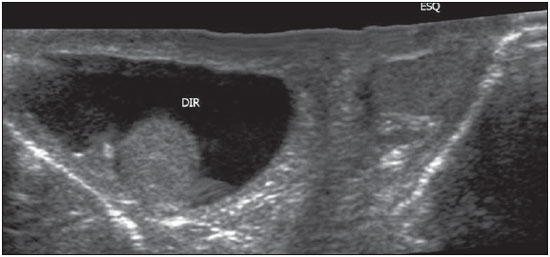

Você também pode utilizar um ultrassom para confirmar o diagnóstico, e ainda fazer o diagnóstico diferencial da massa na bolsa escrotal. Você pode usar o doppler para afastar presença de inflamação, tumores ou varicocele.